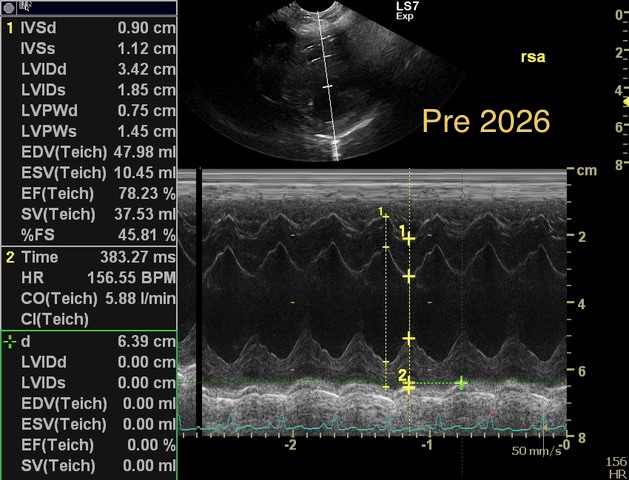

Chronic stage C MVD.TID Pimo and Lasix(high dose), ACEi and Spirono. Doing well. Recheck: Idexx GHP= CBC-NSF ,SDMA 15,BUN 14.1mmol/L, Creat 79umol/L. US: Cornell Indx LVd=1.46(prev2.1), LV septal flattening with diastolic dip,LAAO=2.47,Evel1.45m/s, TVregPG-68mmHg,HV distension-mod ascites.LV and LA underloading via diuretics and PHT (mild PHT past).PHT more pre vs post cap based on small LVsize? Consider Sildenafil/L Arg.Concerned about developing L CHF.Is CHF less likely adding PDE5i with MVD/PHT in underloaded LV than same scenario with vol overloaded LV at similar staging. MVPG=120.3mmHg

Thanks. Not sure if any sig. MV stenosis?? My experience limited.3 PWD from diff times. Ls7 vid. is from 2024,initially thinking reverse remodelling where the lasix lowering preload and Pimo is decreasing LV size via decreased resist/increase cxn while LA no change because it’s a chronic filled remodeled saggy bag receiving Regurge volume??